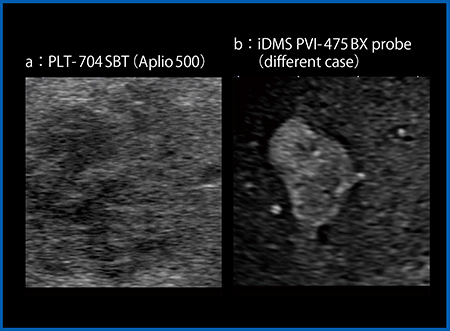

図6は肝血管腫であるが,7MHzのPLT-704SBT(Aplio 500)ではノイズが多く不明瞭である(図6 a)。一方,iDMS PVI-475BXを使用し,ApliPure plus 2とPrecision 2を適用した画像(別の症例)(図6 b)では,位相の変化が明瞭となり,病変内部の糸ミミズサインにより血管腫であると確定診断できる。iDMS PVI-475BXおよびApliPure plusとPrecision Imagingの組み合わせは,腫瘍の質的診断にも有用と言える。

図6 肝血管腫におけるPLT-704SBT(a)とiDMS PVI-475BX(b)の比較